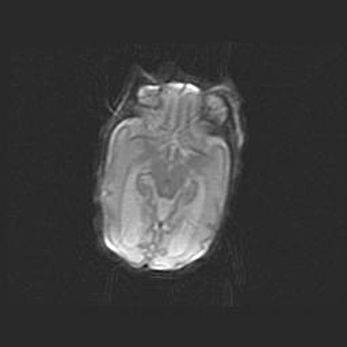

Церебральная ишемия II.

Возраст: 5 дней

Вес: 3400 г

Пол: женский

Окружность головы: 35 см

Срок гестации: 39 недель

Церебральная ишемия – это заболевание, характеризующееся недостаточностью (гипоксией) либо полным прекращением (аноксией) снабжения мозга кислородом по причине закупорки одного или нескольких сосудов. Это приводит к  что метаболическим расстройствам различной степени тяжести в тканях головного мозга, развитию коагуляционных некрозов и гибели нейронов.